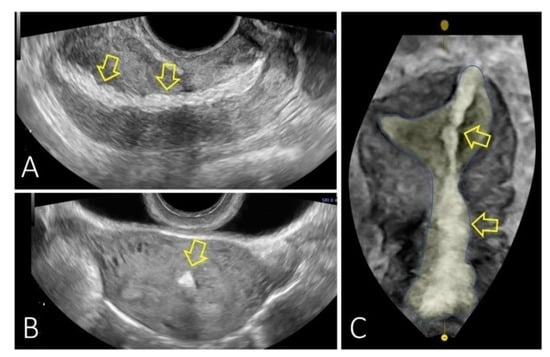

| Ozaki et al. [34] | - Asymptomatic - Referred to a hospital at 16 weeks gestation for a high-risk obstetric consultation | - 2 years later | - D&C | - US: a hyperechogenic structure in the anterior wall of the uterine body with suspected incarceration of the omentum or mesenteric fat | |

| Sedratiet al. [32] | - Amenorrhea - Lower abdominal pain for seven months post-operatively. | - D&C for incomplete miscarriage | - US: discontinuity in the uterine serosa with a hyperechoic mass protruding from the peritoneal cavity into the myometrium suggesting an incarcerated pelvic organ |